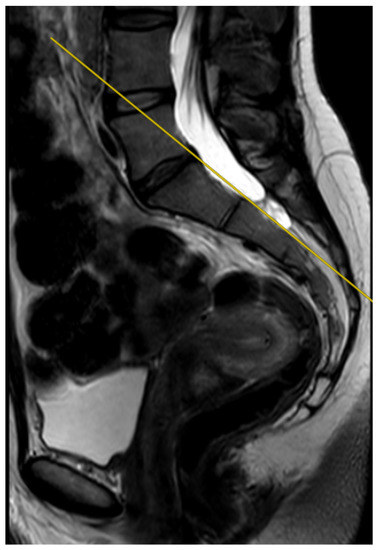

The deviation angles were measured on T2-weighted sequence slices obtained in the sagittal plane, as shown in Figure 1. Figure 2, presented below, shows the interrelationship of the three sequences of the same examination (as shown in Figure 1) that were used in this study. The RadiAnt DICOM Viewer was used to take measurements. All examinations were analyzed by two independent researchers in a blind study. The final results of the measurements were averaged to obtain a single deviation angle corresponding to each examination.

Figure 1.

The measured deviation angle equals 5.3 degrees (group 2). The red line is the fully correct line drawn between the posterior edges of the S1 and S2 vertebrae. The yellow line marks the actual plane in which the slices were acquired.

The measured deviation angle equals 0 degrees, properly performed MRI examination of the sacroiliac joints, T2-weighted sequence. The yellow line marks the actual plane in which the slices were acquired, while it is also the fully correct line drawn between the posterior edges of the S1 and S2 vertebrae.